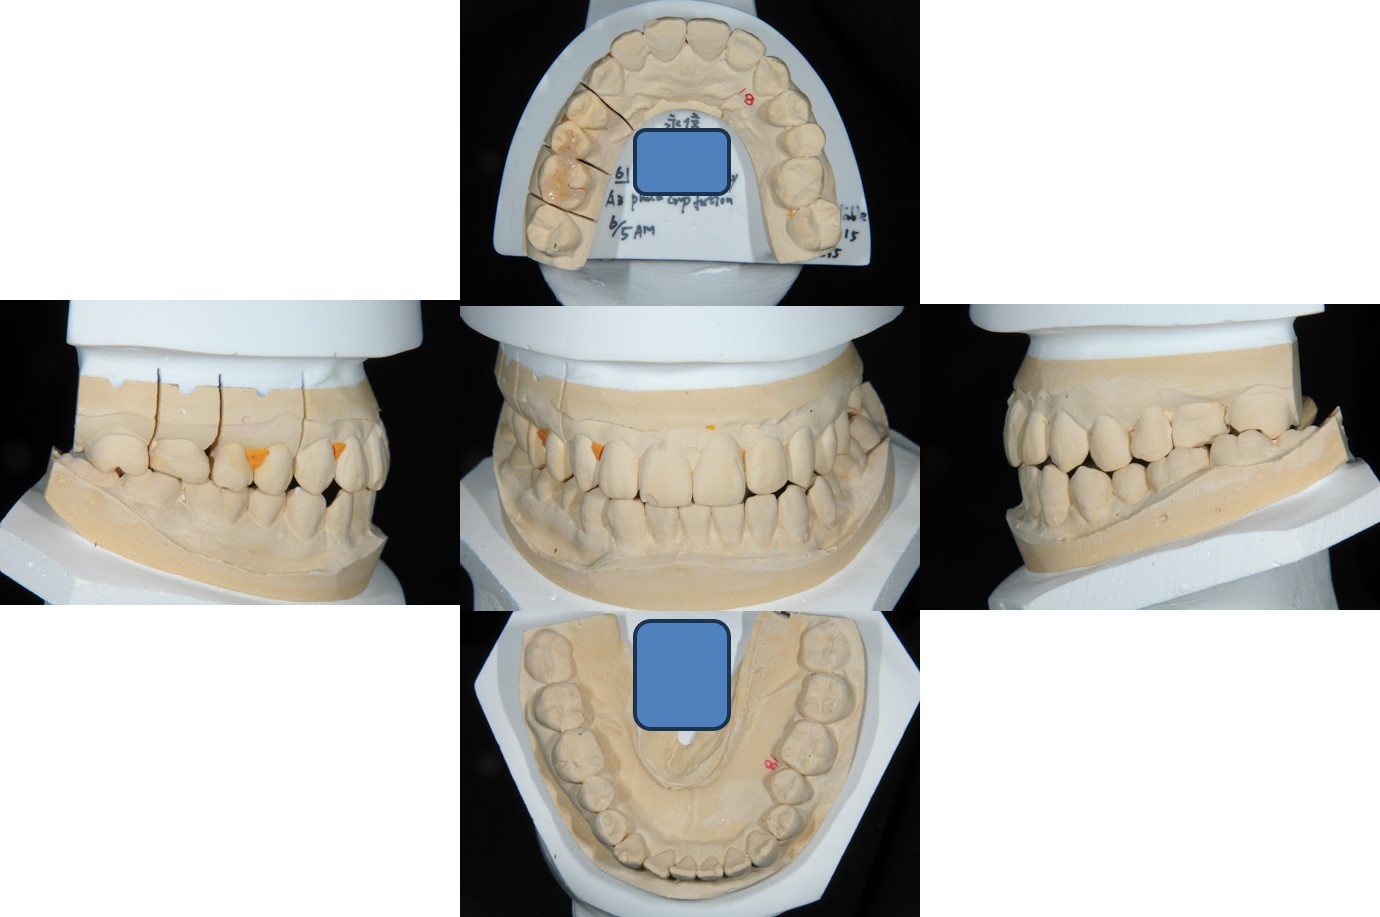

經面弓轉移,上咬合器

技師於咬合器上製作模型